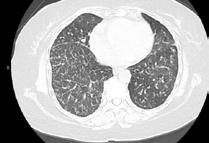

A 58-year-old female with recently diagnosed COVID-19 pneumonia was found to have a dry cough and dyspnoea in the setting of persistent bilateral hilar and mediastinal lymphadenopathy associated with bilateral nodular infiltrates. Of note, she immigrated to the USA from India 10 years prior, with the most recent travel to India 2 years ago. Quantiferon testing upon return to the USA was negative at that time. Workup included bronchoscopy with endobronchial ultrasound revealing non-caseating granulomas with negative stains for acid-fast bacilli (AFB). She was diagnosed with Stage 3 sarcoidosis and initiated on prolonged steroid taper with improvement of symptoms. With taper of steroid dose, however, she developed lymphocyte-predominant exudative effusion with negative cultures, and was reinitiated on a protracted steroid course with rapid symptom resolution. At 4-month follow-up, she had worsening CT findings upon steroid taper, and was started on azathioprine. One month later, she required hospital admission for worsening dyspnoea and fatigue. She was noted to be febrile, tachycardic, and tachypnoeic with worsening

hypoxia. Subsequent CT chest showed progression of bilateral nodular infiltrates with new right upper lobe consolidation and air bronchograms concerning for multifocal pneumonia (Figure 1). Incidentally, she was also noted to have calcified splenic granulomas. She developed rapid clinical deterioration, ultimately requiring mechanical ventilation, pressor support, and continuous renal replacement therapy. Repeat bronchoscopy revealed diffuse alveolar haemorrhage with multiple AFB smears positive for Mycobacterium tuberculosis. She was immediately initiated on quadruple therapy, but unfortunately, despite treatment, developed refractory shock and passed away 2 weeks after initial presentation.

A) Initial adenopathy with peripheral patchy ground glass opacities in the right lung following COVID-19 pneumonia. B) Persistent bulky adenopathy 1 year after initial presentation. C) Extensive nodularity throughout the right lung with increasing confluent opacities in the right upper lobe and stable mediastinal lymphadenopathy 2 years after initial presentation. D) Tuberculosis superimposed on sarcoidosis with progression of nodular infiltrates, worsening right upper lobe consolidation, and air bronchograms with incidental calcified splenic granulomas (not pictured).

Figure 1: CT progression of patient’s sarcoidosis and tuberculosis.